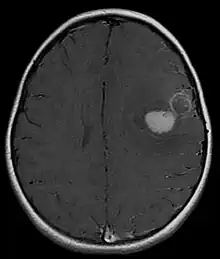

Magnetic resonance image of PNET

Several analysis can be used to determine the presence of the disease. Physical examinations showing papilledema, visual field defects, cranial nerves palsy, dysphasia, and focal neurological deficits are evidences for possible tumor.[2] PNETs can also be spotted through computed tomography (CT) and magnetic resonance imaging (MRI).[2] In images produced by MRIs, an irregular augmentation among a solid mass will indicated the presence of tumor.[3] However, the results of MRIs are usually ambiguous in defining the presence for this specific tumor.[2] In CT scans, the presence of PNETs will be indicated by an elevated density and an increase in volume of the brain.[2] The CT scan can also show calcification,[3] which is present in 41-44% of PNET cases.[2] Since the tumor can be replicated in other parts of the nervous system through the cerebrospinal fluid (CSF), a CSF analysis can also be conducted.[2] A spinal MRI is a fourth type of analysis that is useful in investigating the level of tumor propagation to the spinal cord.[2]